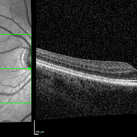

NIR and OCT Right Eye Early Parafoveal Changes Plaquenil

Jan 14 2025 by Kyle D Kovacs, MD

58 year old woman with 11 year history of plaquenil use with early parafoveal outer retinal attenuation and bull's eye on near-infrared imaging. Right eye.

Condition/keywords: OCT, plaquenil toxicity